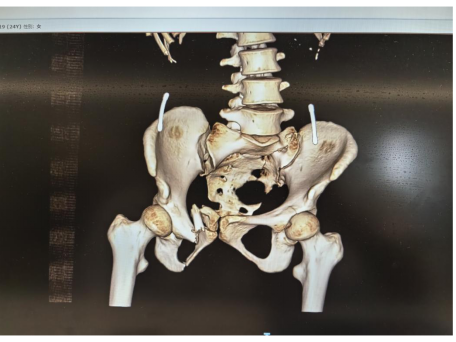

7月2日,在刘华水的指导下,孙延斌、李上再次为患者实施手术。李上介绍说:“这一次所实施的骨盆骨折切开复位螺钉内固定术,主要解决耻骨相关问题,包括清理骨折断端,使用精准微创技术复位螺钉固定,以及双侧骶髂螺钉固定,另外还进行了右下肢损伤部位切开清创。这一切处置措施,都是在生命体征平稳的基础上进行的,本次手术有助于患者进行肢体功能康复训练。”

图片

*2025年7月2日第2次手术后